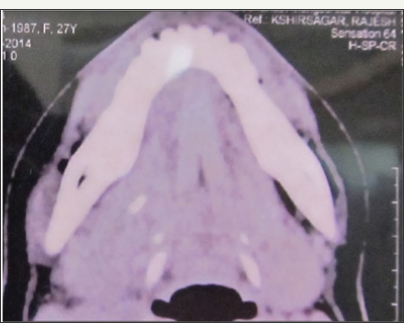

A young female reported with a complaint of painful swelling in the right submandibular region (Figure 8). The swelling was present since four to five months. Initially, the swelling was intermittent and was associated with meals. Swelling persisted for one to two hours after food and then gradually subsided. The patient consulted a maxillofacial surgeon and was diagnosed with right submandibular sialolith in posterior portion of the duct and was advised for surgical removal of the sialolith. Since the patient was residing away from home (job placement), so she opted for removal at her hometown. When the patient reported to us (delay of about 1 month since consultation with surgeon), she complained of persistent and painful swelling. On examination, right submandibular region was swollen and tender on palpation. Slightly turbid fluid was expressed from ipsilateral Wharton's duct orifice on glandular massage. Salivary flow was absent. Orifice was normal in appearance. A computerised tomogram was already done and showed a sialolith of 6.1mm in right posterior Wharton's duct (Figure 9a-9c). Patient was prescribed broad spectrum antibiotics and the surgical removal was planned under general anaesthesia.

Figure 9b: Axial section showing the location of the radiopaque mass to be behind the third molar region.

Figure 9c: Axial section showing the location of the radiopaque mass to be behind the third molar region.